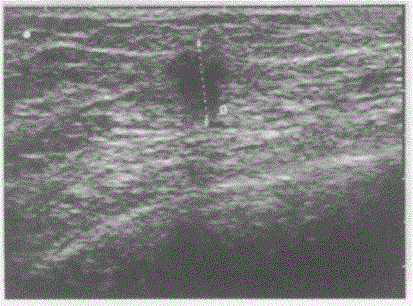

问题 临床资料:女,39岁,常规体检。 超声综合描述:右乳外上象限腺体层内可见1.4cm×1.2cm类圆形低回声区,边界清,内回声不均。 超声提示:

选项 A.乳腺脓肿 B.乳腺增生结节 C.乳腺癌 D.乳腺纤维腺瘤

答案 C